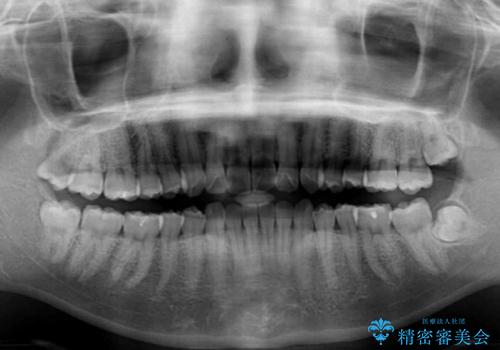

インビザライン矯正で前歯のデコボコを改善

- 前歯のデコボコを気にして来院された患者様です。

目立たないことを最優先にしたいとのことで、デコボコは軽度であったことから、インビザラインにて矯正治療を行うこととしました。

骨格的に下顎骨が左にずれており、上下の正中一致は困難ではありましたが、IPR(歯と歯の間を削る)や後方への移動など組み合わせて、できる限り改善しました。

インビザラインはマウスピースを外している時間が長いと、長期間使用しても前歯のデコボコはあまり改善されません。こちらの患者様は治療期間が長くなり、装着時間が短くなってしまったことで、気になる部分の改善により長期間を要するようになってしまいました。